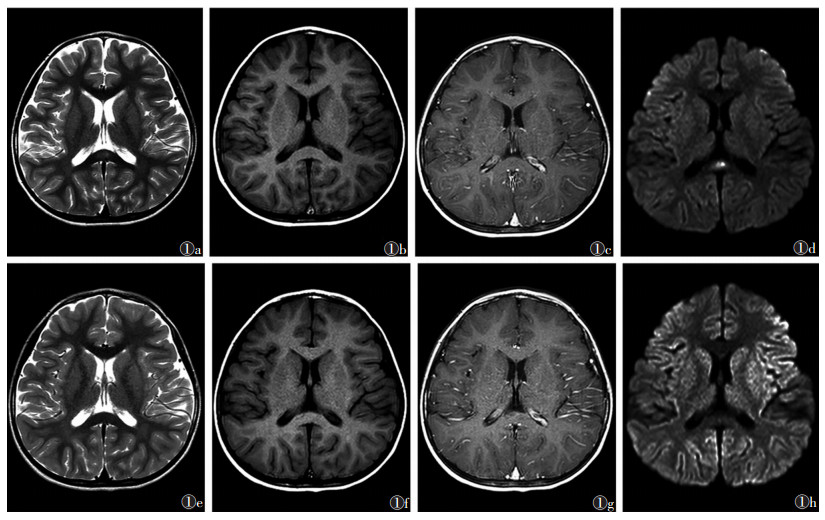

4例均以流感样上呼吸道感染症状首发, MRI均表现为局限于胼胝体压部的圆形或椭圆形边界清晰的孤立性病变, T2WI呈高信号(图 1a), T1WI呈稍低信号(图 1b), T2-FLAIR呈高信号, 增强扫描无强化(图 1c), DWI呈高信号(图 1d), ADC呈低信号, 其中1例除以上影像表现外还累及胼胝体膝部。4例经抗感染、抗病毒和激素等对症治疗后, 临床症状完全缓解, MRI复查脑部异常信号完全消失(图 1e~1h)。住院时间9~25 d, 门诊及电话随访均未出现任何神经系统后遗症。

图 1 女,5岁,因间断发热、呕吐6 d并抽搐入院   图 1a~1d  入院首次MRI检查,提示胼胝体压部椭圆形、边界不清的病灶   图 1a   T2WI呈稍高信号   图 1b   T1WI呈稍低信号   图 1c   T1WI增强扫描病灶无强化   图 1d   DWI呈高信号   图 1e~1h  分别为治疗12 d症状明显好转后复查的T2WI、T1WI、T1WI增强扫描、DWI图像,均示胼胝体压部异常信号基本消失